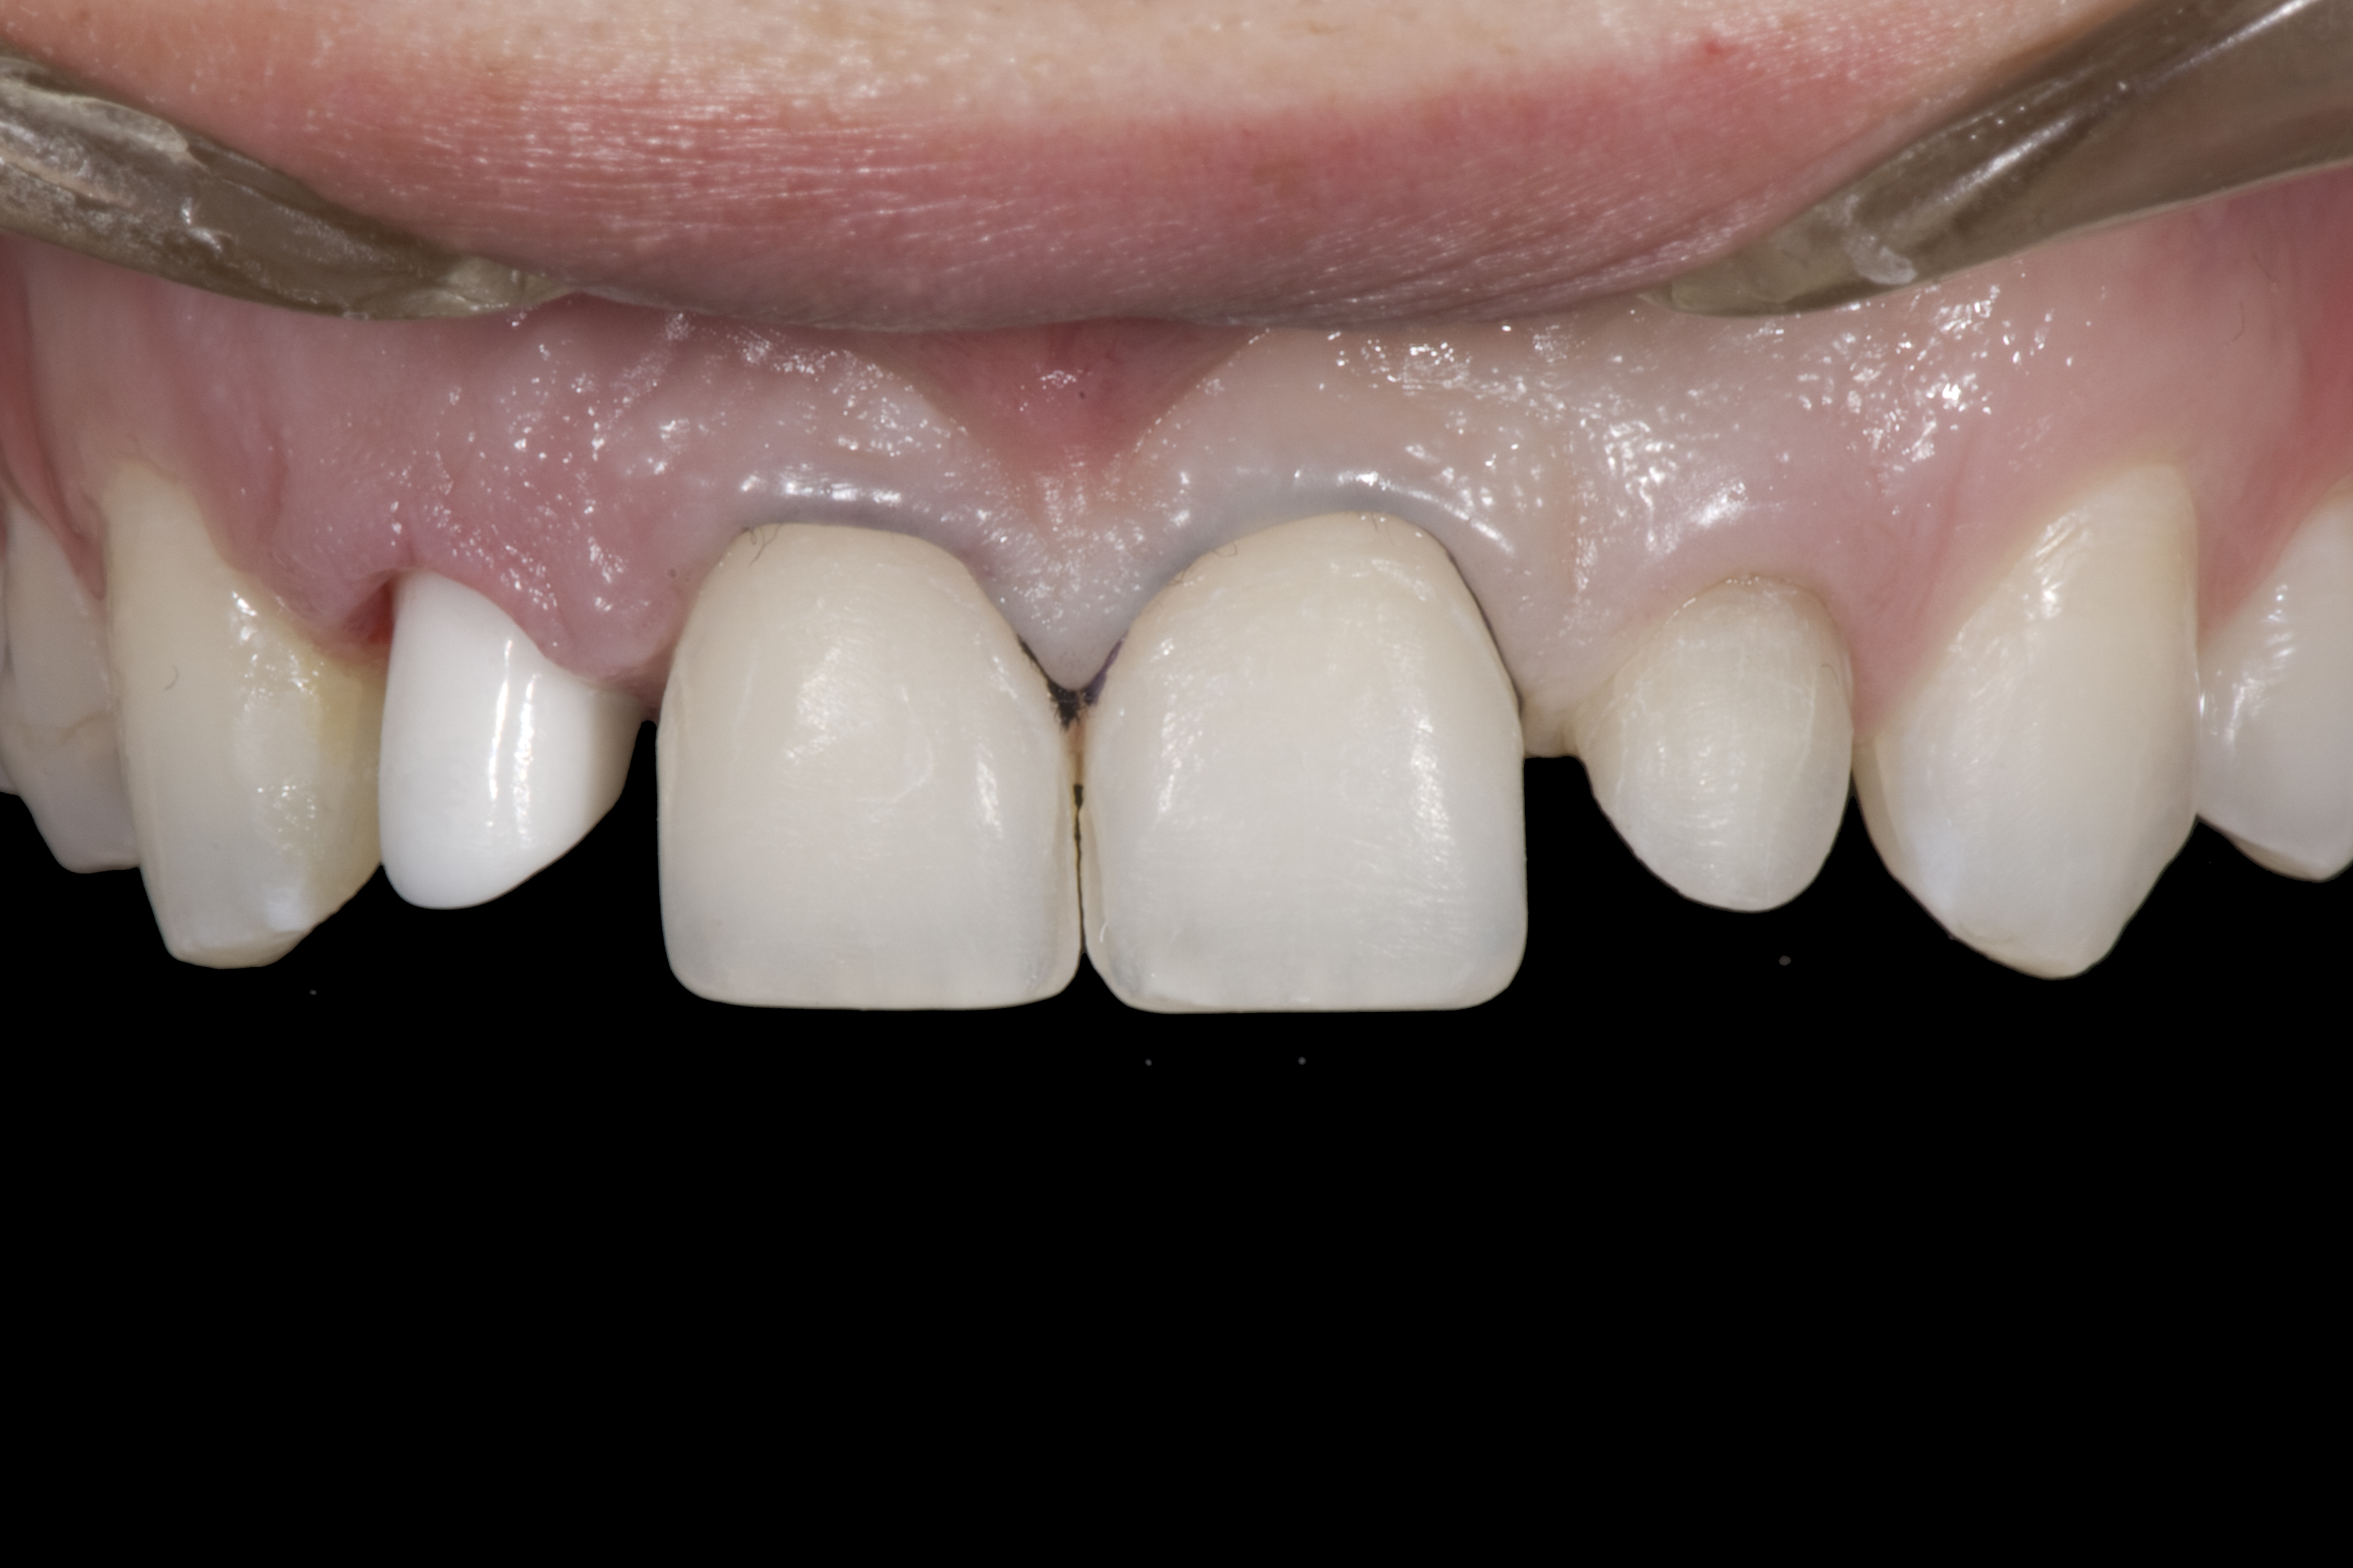

A 14-year-old patient presented to the office with his mother (Figure 1). His chief complaint involved the large spaces between the teeth created by his missing right maxillary lateral incisor and his small left maxillary lateral incisor. He desired to replace the missing tooth with an implant and create a beautiful smile. Upon examination, he was found to have a class I canine and molar relationship, but because he had a tooth size/arch size discrepancy and space distal to the right central incisor, the remaining incisors had drifted to the right. The left maxillary lateral incisor was peg-shaped and in a cross bite position. Studies have shown a clear association between congenitally missing teeth and reduced tooth size.59-62 Because he was only 14-years-old at the time and could not have implants placed until the cessation of growth (somewhere in the vicinity of 22 years old), he was sent to the orthodontist for alignment of the teeth.16,17 After 2 years of orthodontics, the appliances were removed, and his tooth coloration was improved using carbamide peroxide bleaching (Figure 2). Because some form of provisional needed to be placed until he was finished growing, a double-wing metal resin-bonded bridge was chosen. As discussed earlier, this is the ideal transitional prosthesis for patients that have congenitally missing maxillary lateral incisors. The benefits of this type of prosthesis include its ability to be removed and rebonded during the surgical phase of treatment and its ability to retain the roots in their proper position after orthodontic treatment.16 The final plan for the patient was to increase the width of the central and the maxillary left lateral incisor, utilizing porcelain laminate veneers to achieve the appropriate width/length ratio of 80%. A wax-up was created to idealize tooth size, a putty matrix was made from the wax-up to facilitate bonding of the incisors, and a non-precious, double-wing metal resin-bonded bridge was fabricated for lateral incisor replacement. Once the teeth were bonded to ideal size, the “Maryland Bridge” was fabricated from a polyvinyl arch impression with the newly bonded teeth (Figure 3). The metal frame was cast from a non-precious alloy to allow for fabrication of a very thin frame and to create a better surface for bonding. After sandblasting the internal aspect of the frame with CoJet™ silica (3M ESPE), accomplishing salinization, and executing cementation with a dual-cure resin cement, a fairly good adhesion to the frame was anticipated.29 The enamel surface was etched with phosphoric acid for 30 seconds, the primer (Single Bond Plus, 3M ESPE) was applied to both the internal surface of the sandblasted framework and the etched enamel, and the bridge was cemented with RelyX™ ARC (3M Espe) dual-cured resin cement (Figure 4 and Figure 5).

(13.) Deficient ridges in the areas of the missing lateral incisors.

Figure 13

(14.) Occlusal view. Some form of augmentation would be needed if implants were being considered.

Figure 14